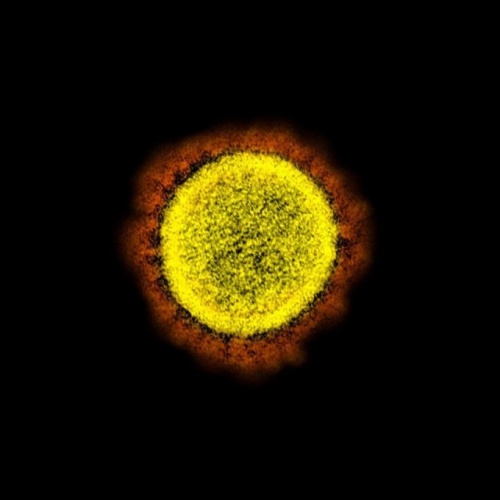

ABD'de yapılan bir çalışmada, yeni tip koronavirüsün (Covid-19) insan hücrelerindeki yayılışı elektron mikroskobuyla görüntülendi. ABD'li bir hastadan alınan Covid-19'la enfekte olan hücreler laboratuvar ortamında çoğaltılarak virüsün en net görüntüleri kaydedildi.

VİRÜSÜN EN NET GÖRÜNTÜLERİrnMedikal görselleştirme uzmanları, virüsü sağlıklı hücrelerden ayırmak için renklendirdi. Yapılan çalışmada korona virüsün insan hücrelerinde yarattığı tahribat tüm yönleriyle açığa çıkarıldı.

Burada bir tarama elektron mikroskobu altında görülen yuvarlak sarı nesneler Covid-19'a neden olan virüsleri gösteriyor.

Diğer bir fotoğrafta ise, virüs partiküllerine adını veren dış kenarındaki sivri uçları açıkça gösteriyor. 'Corona' Latince taç veya hale anlamına geliyor.